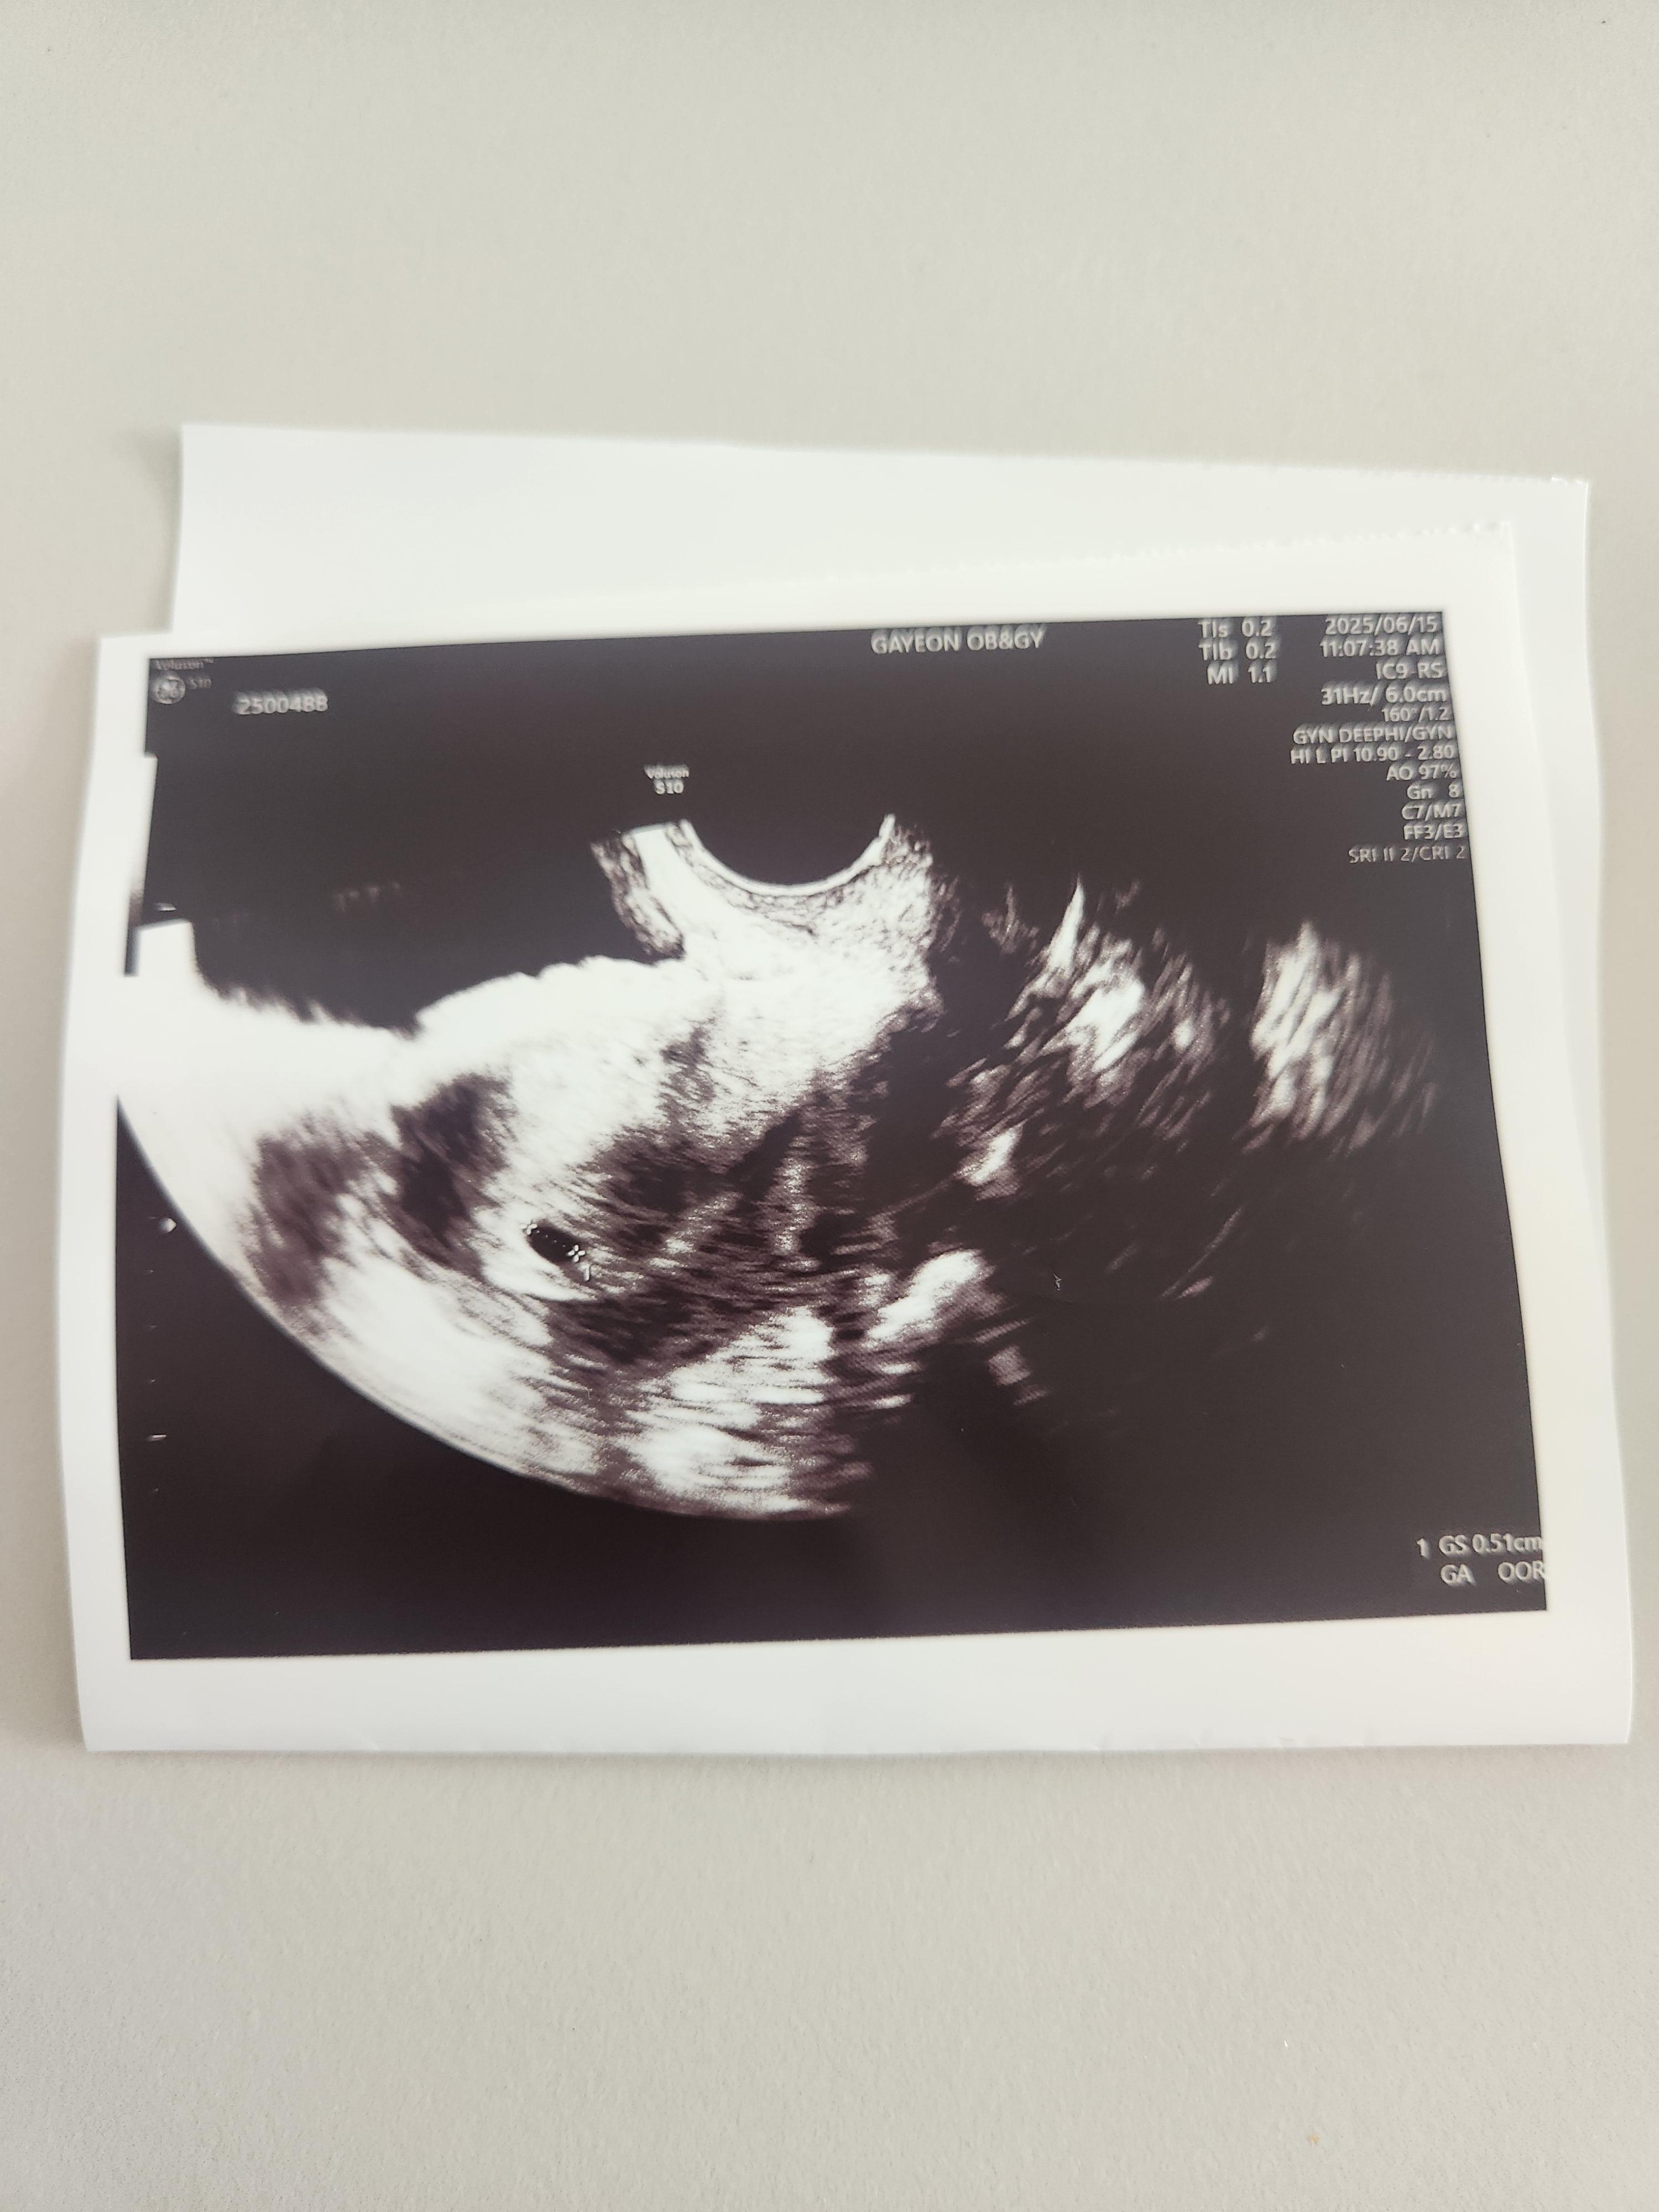

초음파는 질 초음파로 봤고, 아기집을 조그마하게 확인할 수 있었습니다.

아직은 심장소리를 들을 수는 없었고, 주수가 얼마 안돼서 아기집만 볼 수 있었습니다.

일주일 사이에 아기집을 잘 지어놨고, 피고임이나 다른 이상한 것도 없다고 말씀해 주셨습니다.